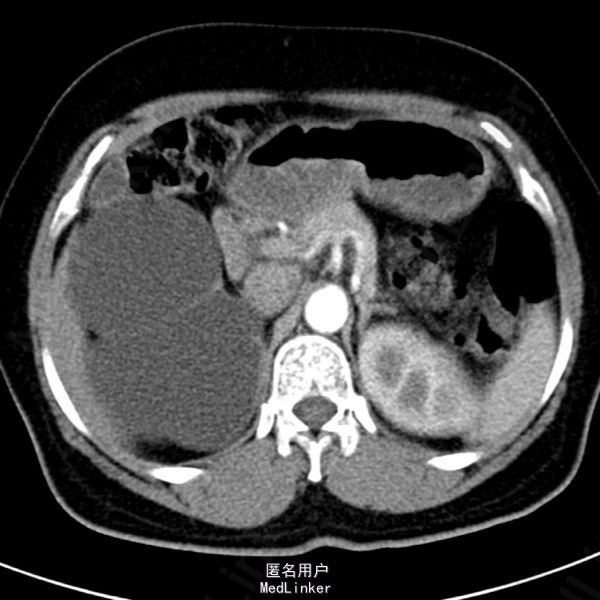

患者女,62岁11月,因“体检发现右肾积水4天”入院。自诉无任何不适。

超声检查示:1.右肾重度积水 2.右肾结石,疑右侧输尿管起始端结石 SPECT肾显像示:右肾无功能;左肾GFR代偿性增高,左上尿路引流通畅。

诊断:右输尿管上段结石 右肾重度积水无功能。行腹腔镜右肾切除术。术中见患者右肾实质菲薄,体积较大,与周围组织粘连重,穿刺吸出淡黄色尿液约1200ml。